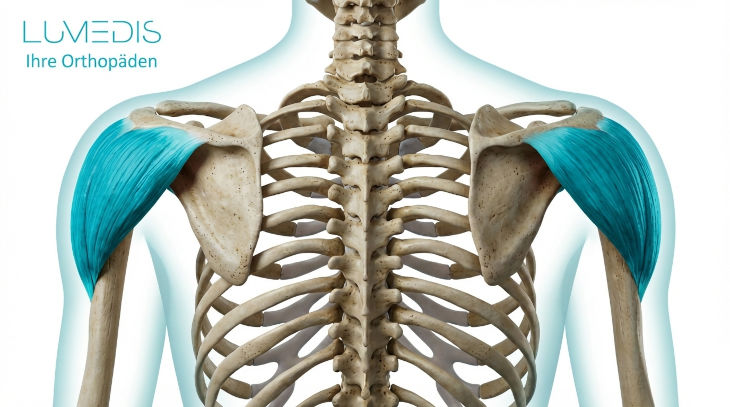

Abbildung einer Schulter von hinten:

1. Musculus supraspinatus

2. Musculus infraspinatus

3. Musculus deltoideus

Abbildung der hinteren Rotatorenmanschette

Abbildung der Rotatorenmanschette